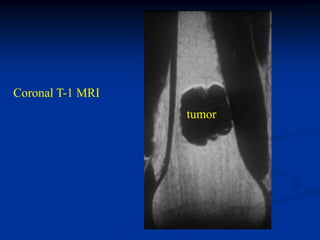

Case #120

38 year female

enchondroma

distal femur

Bone scan

Coronal T-1 MRI

tumor